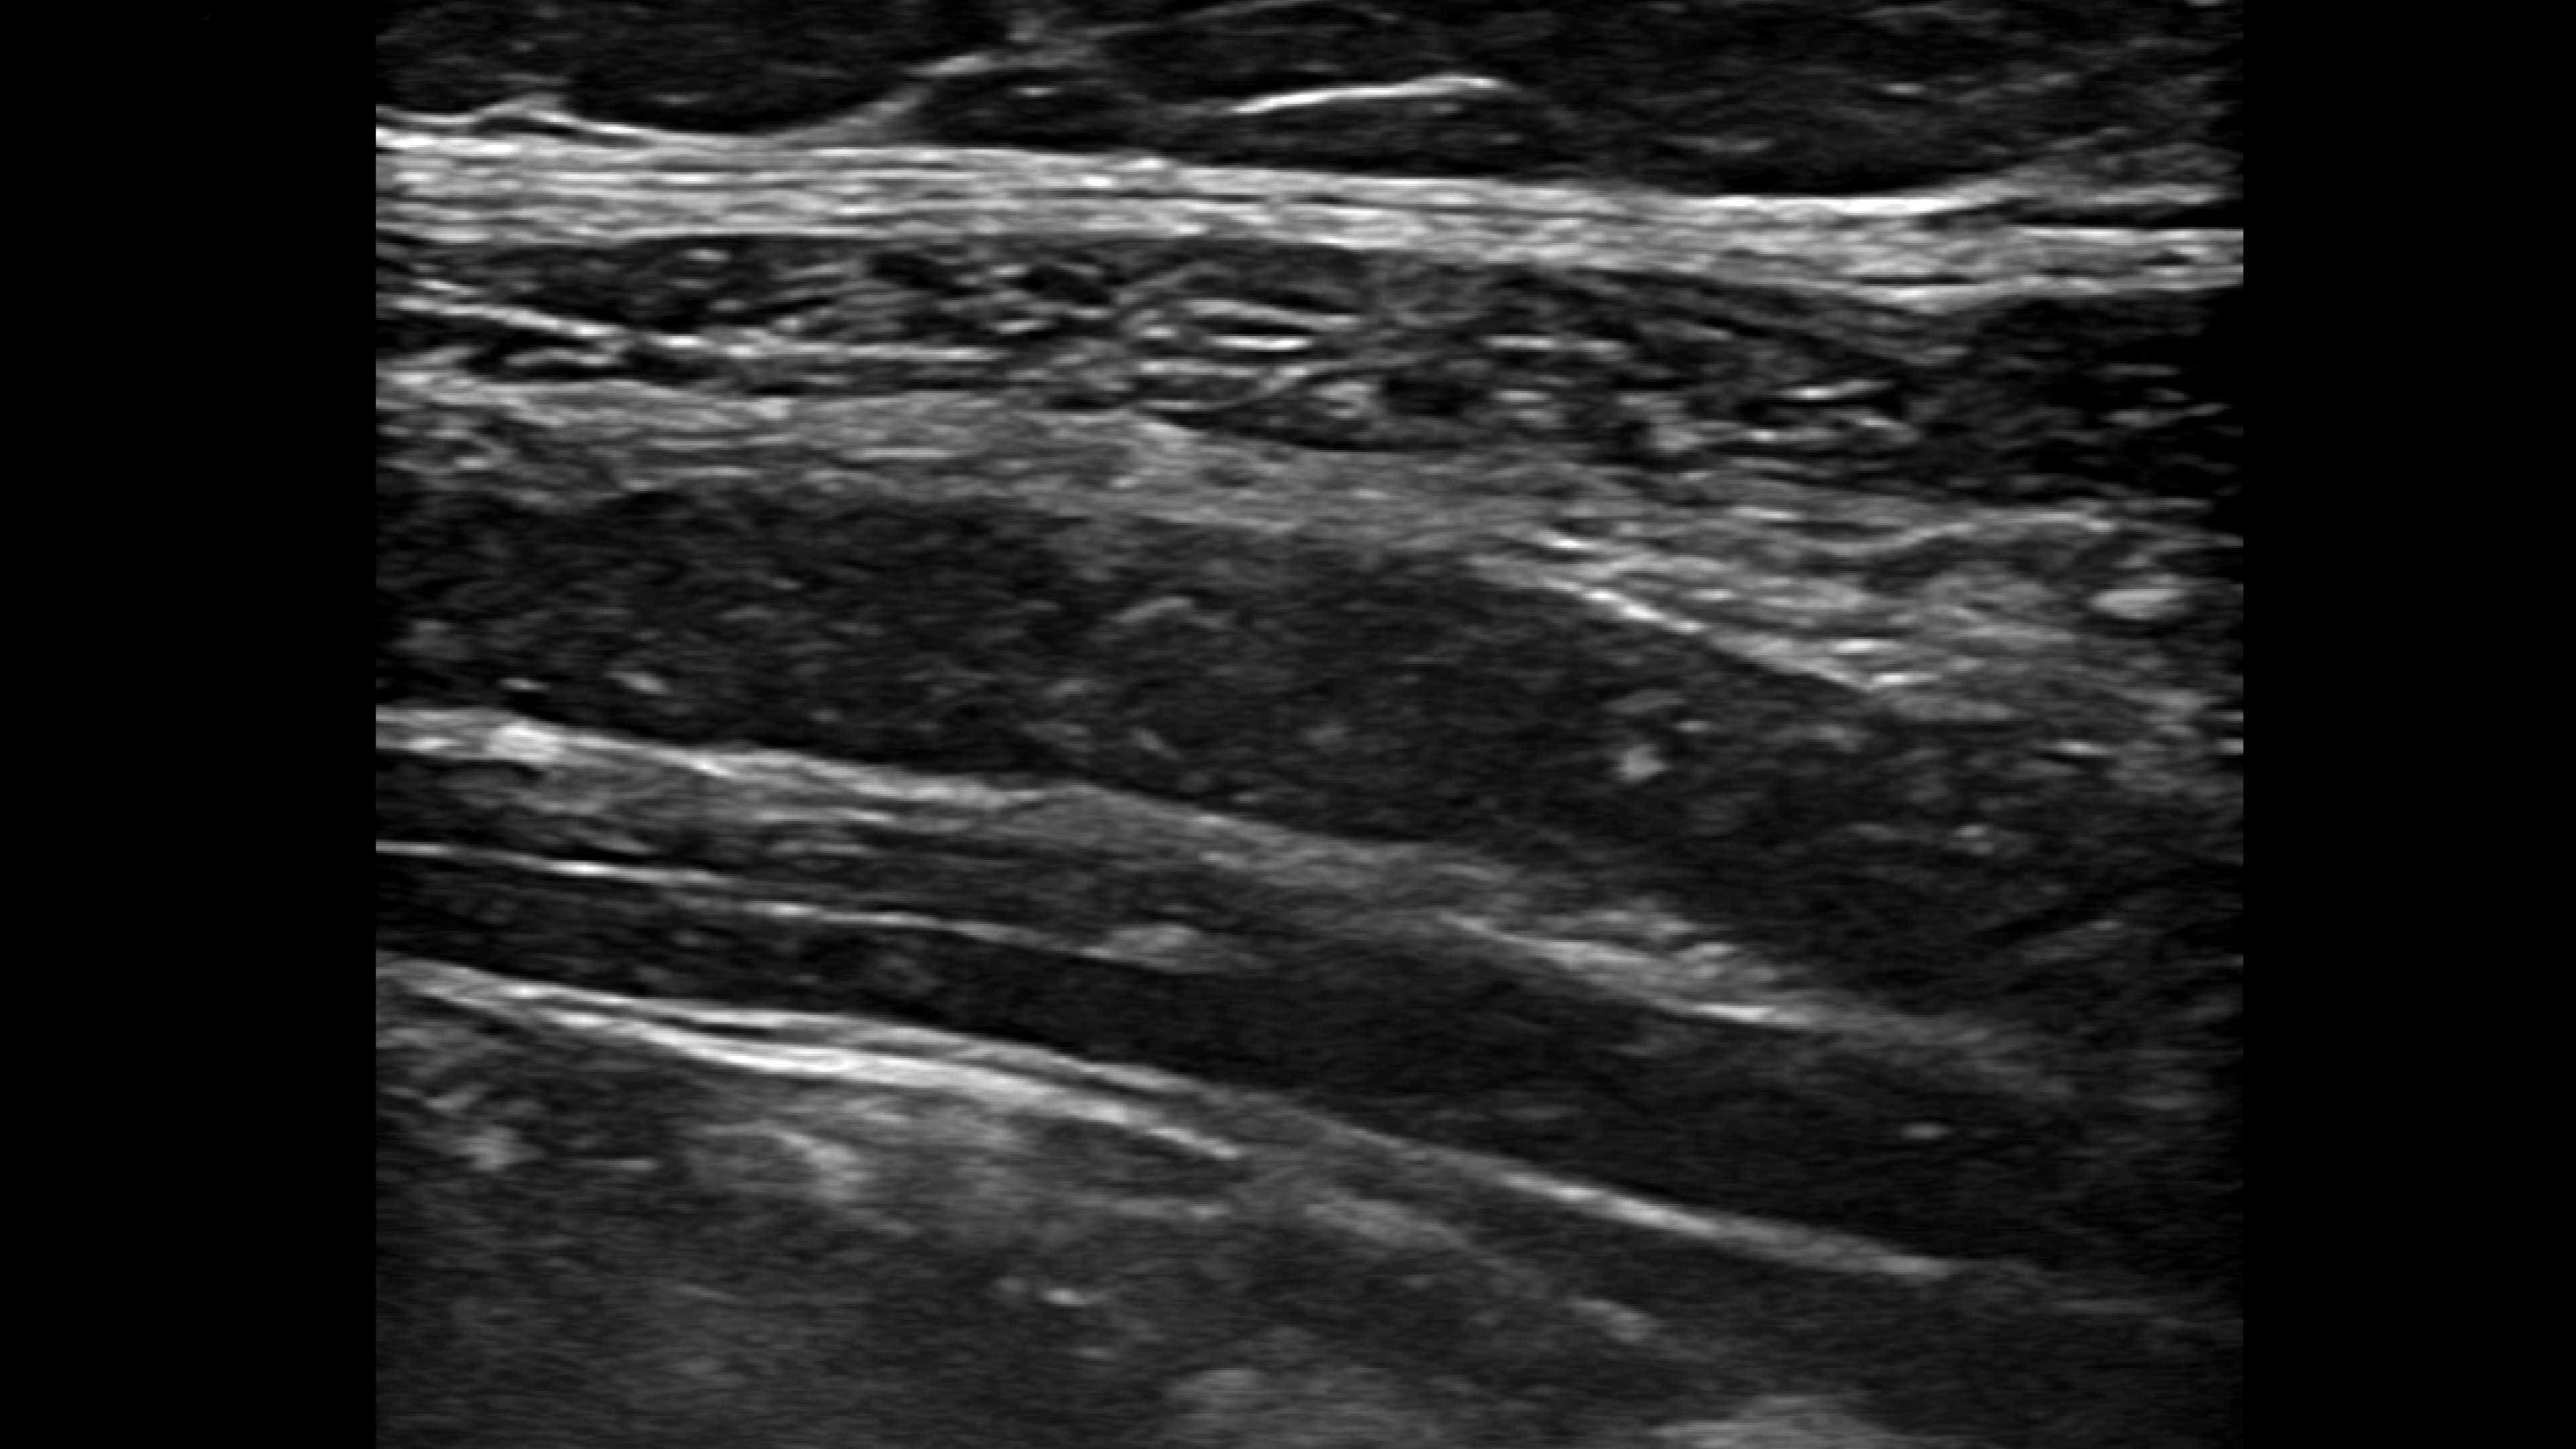

Musculoskeletal (MSK)

A curved array on one side and linear array on the other of the dual wireless probe enables clear assessment of deep and shallow anatomy without switching probes.